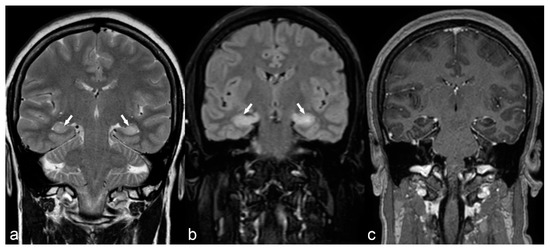

Auto-immune encephalitis is a less frequent cause of epilepsy characterized by high T2/FLAIR signal of the temporal lobe (including the hippocampus), insula and cingulum, usually with bilateral symmetrical or asymmetrical involvement (Figure 13).

Figure 13.

50-year-old woman. Symmetrical hyperintensity is identified on coronal T2WI (a) and FLAIR (b) in both hippocampi (arrows). No abnormal enhancement is seen on 3D T1 Gd (c). This is a case of autoimmune limbic encephalitis.